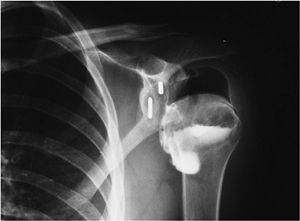

FIGURE 7-24 AP radiograph of an arthrogram demonstrating a recurrent tear with contrast in the subdeltoid bursa (arrows). Note the resected clavicle (large arrow).